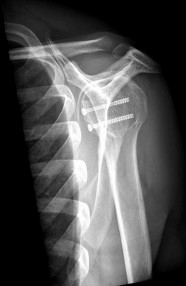

Question 6:

A 68-year-old female underwent a total hip arthroplasty (THA) utilizing a ceramic-on-ceramic bearing surface one year ago. She now complains of a loud, audible squeaking sound originating from her hip during normal ambulation. Which of the following factors regarding component positioning is most strongly associated with this complication?

Explanation:

Squeaking is a known complication specific to hard-on-hard bearing surfaces, most notably ceramic-on-ceramic THA. The primary etiology is edge loading, which disrupts the fluid film lubrication. Edge loading is most frequently caused by acetabular cup malposition, specifically excessive abduction (a 'steep' cup) or version errors, as well as impingement leading to micro-separation.